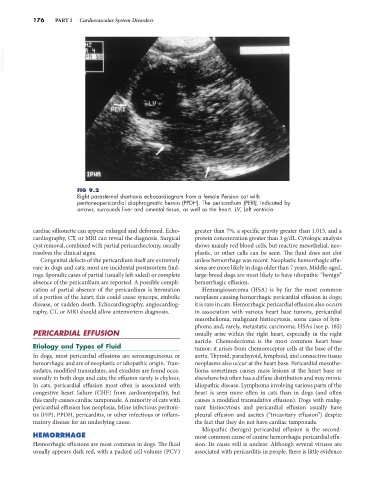

FIG 9.2

Right parasternal short-axis echocardiogram from a female Persian cat with

peritoneopericardial diaphragmatic hernia (PPDH). The pericardium (PERI), indicated by

arrows, surrounds liver and omental tissue, as well as the heart. LV, Left ventricle.